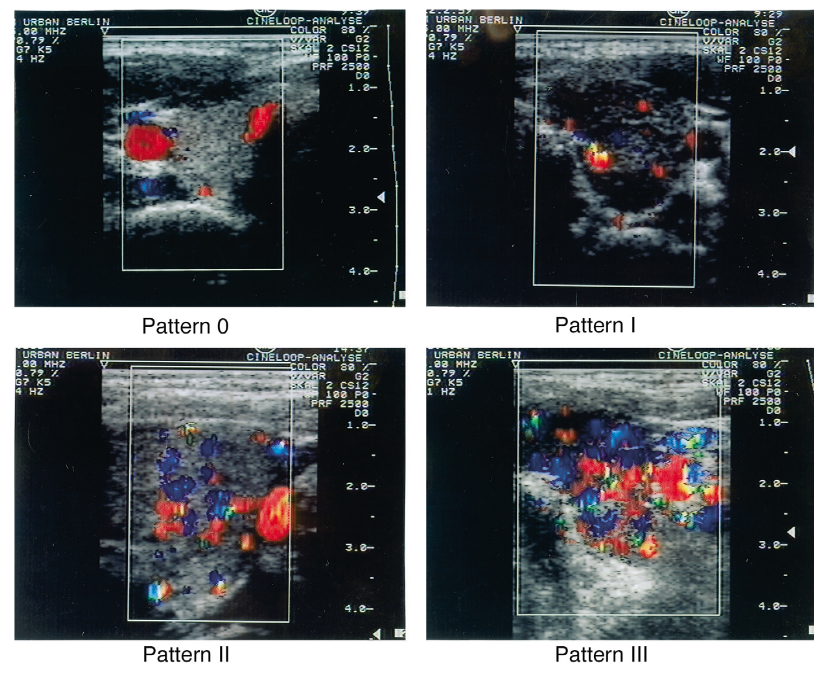

Pattern d'hypervascularisation Doppler dans les hypothyroïdies

Réglages : PRF à 2'500 Hz et gain couleur à 80%.

• Pattern 0 : flux sanguin limitée aux artères thyroïdiennes périphériques, avec flux intraparenchymateux absent, correspondant à un aspect normal ;

• Pattern I : flux intraparenchymateux un peu augmenté ;

• Pattern II : flux couleur intraparenchymateux clairement augmenté, avec distribution diffuse et homogène ;

• Pattern III : flux couleur intraparenchymateux augmenté de manière marquée avec distribution diffuse et homogène, correspondant à l'aspect "thyroid inferno".

Source : European Journal of Ultrasound - Color Doppler sonography in hypothyroidism